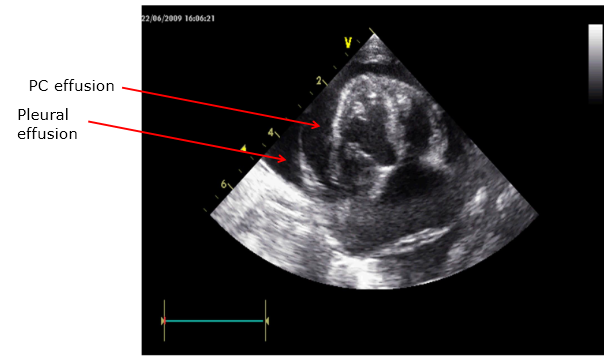

Comment on the principle features evident on the echo, in particular the relative sizes of the cardiac chambers and the thickness of the ventricular walls.

Do you know how these images might be generated?

24 hours later he is much more stable

An echocardiogram was performed